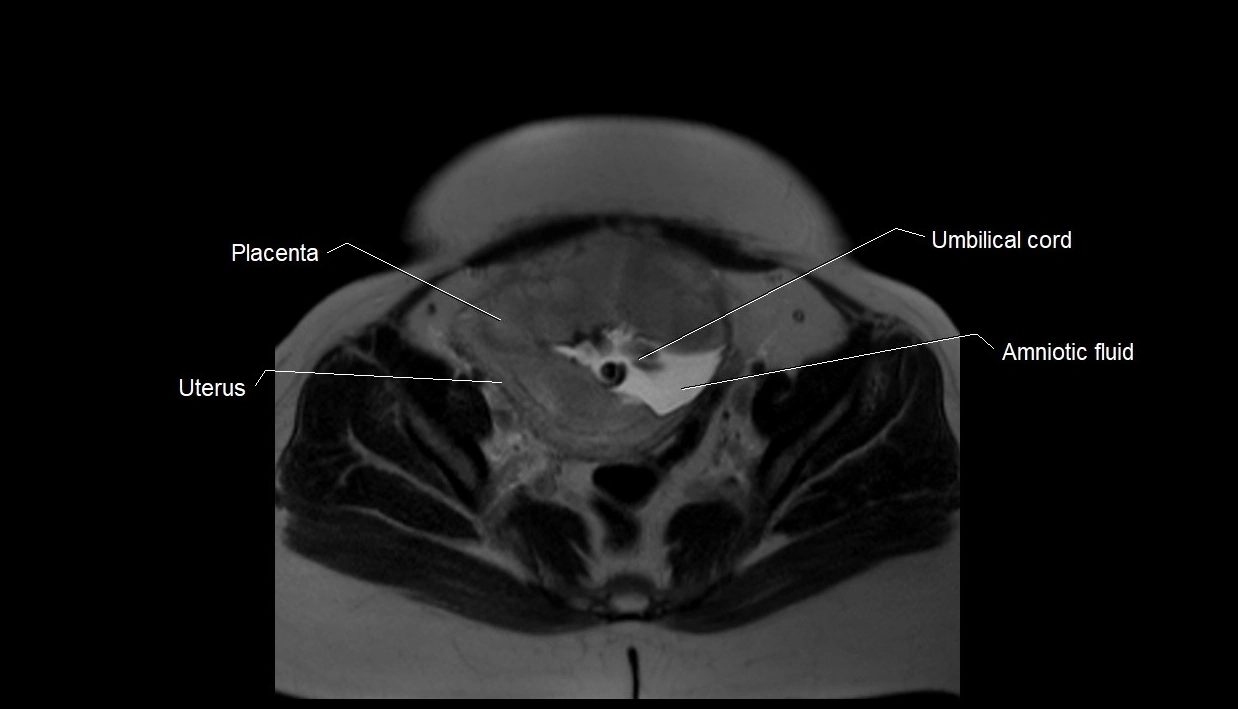

MRI Appearance

T2 HASTE (T2 GRE):

• Amniotic fluid shows very bright hyperintense signal

• Provides natural contrast against fetus and placenta

• Small particles (vernix) may appear as scattered hypointense foci within bright fluid